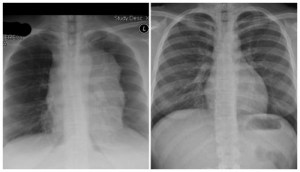

In April 2007 I went to a walk-in clinic because of flu-like symptoms. After a chest x-ray, the doctor’s words were “I have never seen anything like this before” and I was admitted to the emergency room. There, they confirmed that I had a mass sitting on my heart and my lung and I was transported to the University of Washington Medical Center. Weeks later, at the age of 29, I was diagnosed with stage 4 Hodgkin’s Lymphoma.